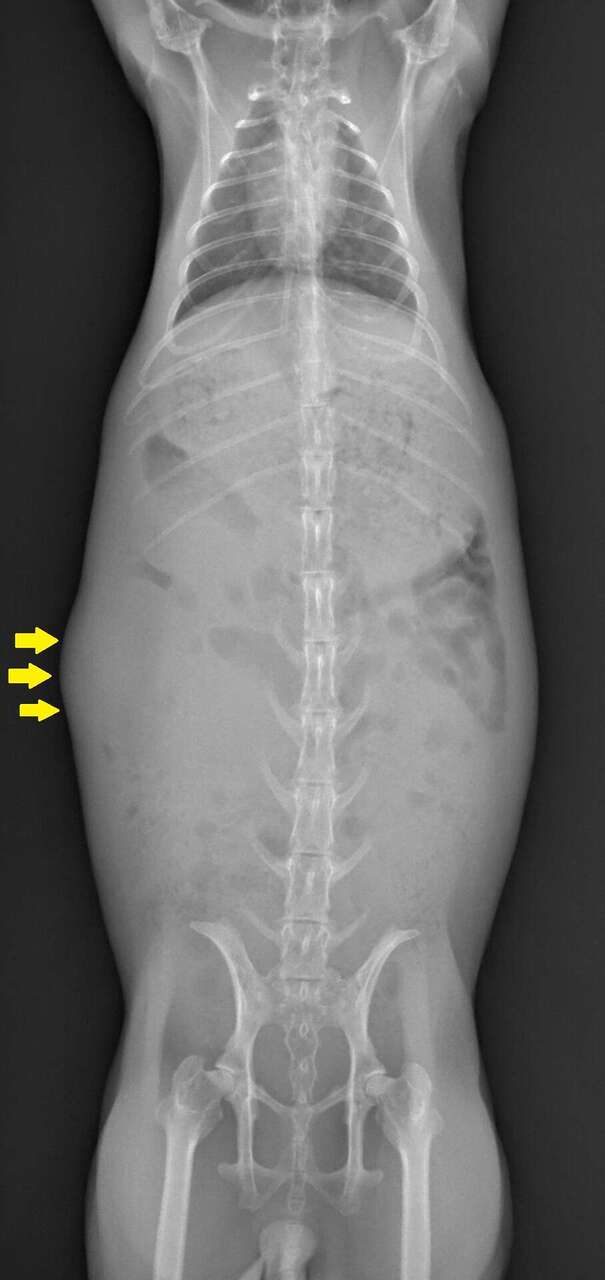

レントゲン検査にて胃拡張と消化管ガスの貯留と共に右の中腹部に膨らみが認められました。

CT画像でも右腎嚢胞は巨大であり、腎臓の正常な構造は消失していました。